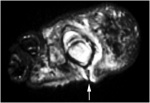

Рис.8. OM and sinus tract MT Head

МРТ - Остеомиелит и свищевой ход: головка плюсневой кости